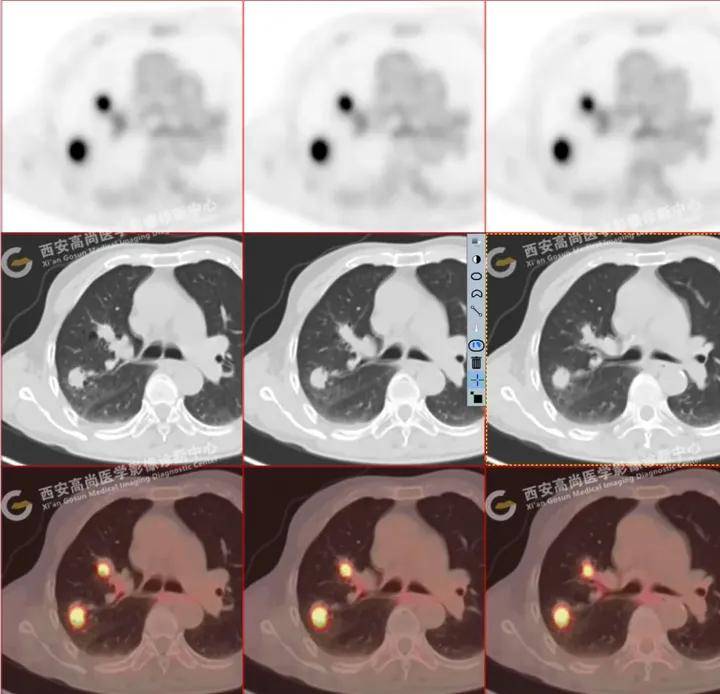

【高尚病例】多发肺结节病例:重症感染 | 惠普尔养障体肺炎_密度_症状

图片尺寸1080x909

病例1 双肺多发结节 男47岁,胸闷,胸痛,咳嗽,发热10余天;家庭常年行

图片尺寸750x761